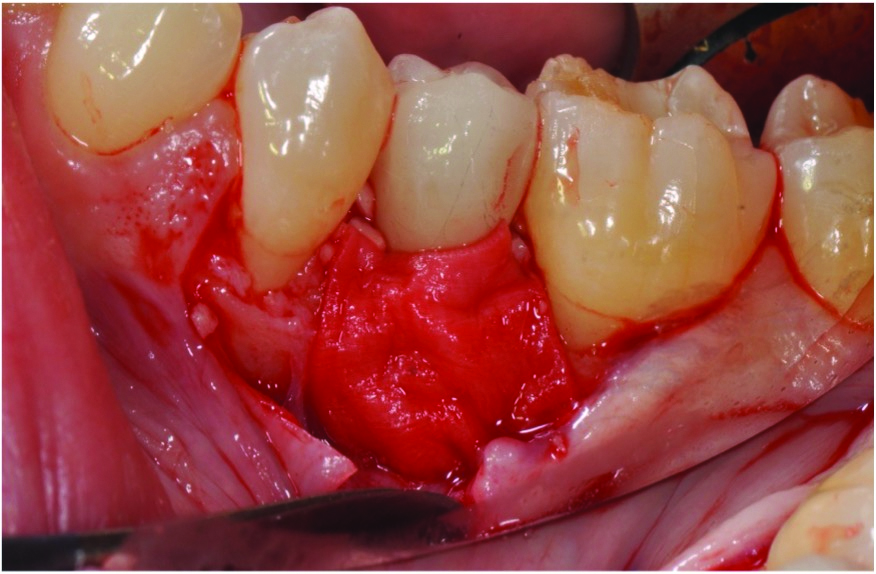

Curettes with small tips were used with ultrasonics to thoroughly clean the intrabony defect while not touching the implant surface (Figure 3 and Figure 4). The surface valleys and threads were carefully cleaned using an air polisher (sodium bicarbonate) for 1 minute, followed by sterile water irrigation of the site for 1 minute. After air drying, EDTA was applied for 1 minute, followed by sterile water rinse for 1 minute, with the previous steps repeated. The FDBA bone graft was soaked in sterile water, dried with a 2 x 2 gauze, and soaked in rhPDGF-BB (Figure 5).51 The bone graft was firmly packed into the defect with slight overpacking above the crest (Figure 6). A collagen membrane was divided in half and soaked in rhPDGF-BB. The collagen membranes were then adapted buccally and lingually with slight overlapping interproximally for graft containment (Figure 7). The flaps were passively positioned coronally and interproximally using nonresorbable 6-0 polypropylene sutures (Figure 8).

Fig 3. Granulation tissue was visible after degranulation of the defect.

Figure 3